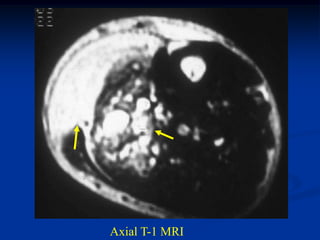

Case #314.1             Angiosarcoma Thigh

52 yr old male with

tender mass in proximal

anterior thigh area 3 mos

Axial T-1   STIR

Cor STIR   Sag STIR